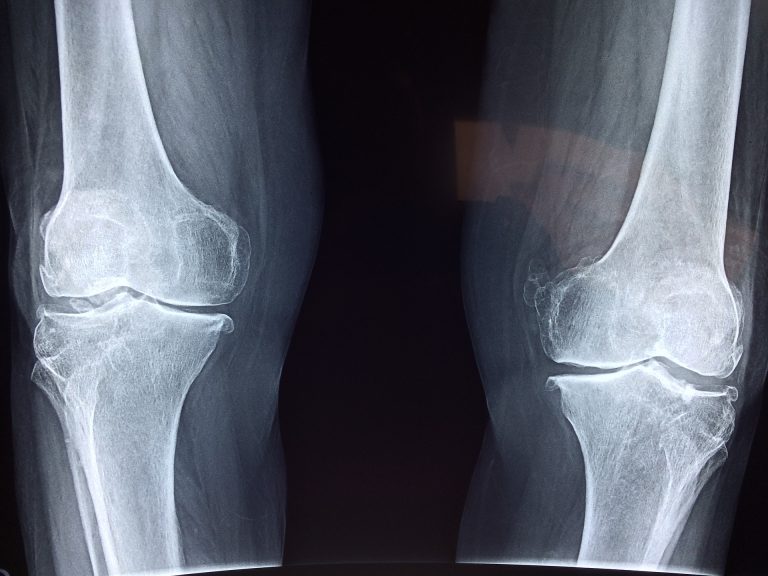

Knee Injury Compensation for Injured WorkersWalker Law Group has over two decades of experience in assisting workers injured in the workplace to achieve the best possible compensation. Walker Law Group are approved by the WorkCover Independent Review Office which has established the Independent Legal Assistance and Review Service. Under this service free access is provided to independent legal advice for injured workers through a financial grant where there is disagreement with an injured worker's insurance company concerning entitlements.Walker Law Group works with WIRO to assist with grants of legal service or to resolve disputes that cannot be progressed. Where there is an arguable chance of success, a grant will be provided which allows Walker Law Group to assist with the particular matter.Injuries that occur in the work place are common. In particular, knee injuries frequently occur due to the fact it is a part of the body that is easily injured in a fall, collision or when turned in a direction not compatible with the knee joint.If you are an employee or sub-contractor who has experienced an injury whilst at work, for example an injury to your knee by way of a fall, collision or stress over time, you may be entitled to a considerable amount of compensation which reflects as best as possible the extent of the injury and assists with any needs which arise as a result of the injury.There are a number of aspects which require consideration before it is possible for a person to claim compensation or bring legal action for the purpose of compensating them for a work place injury.Firstly, you must be either an employee or sub-contractor who receives a wage or commission. If you are an independent contractor, you usually won't be able to make a claim against the organisation which has contracted with you.Secondly, the injury must be work related. This means the injury must have either occurred at the place at which you work, or the work for which you are paid aggravated a pre-existing injury. This includes not only physical but also psychological injuries. Further, if you are caused to suffer a disease the main cause of which is your work or it aggravated an underlying disease, you may be able to bring a claim for compensation. For example, if you work in an area which is loud and this causes damage to your hearing or deafness, or if you work in an area with chemicals which cause damage to your respiratory system including asthma, you may be entitled to compensation.If you are injured travelling to or from work, a claim for worker’s compensation will not normally be successful. If your injury involves a motor vehicle accident when travelling to or from work, it may be covered by the compulsory third party insurance scheme. If there is a 'real and substantial' connection to the injury and your employment however, a claim for compensation may be successful.Where an employee or sub-contractor is injured at work and the employer or organisation contracted with notifies their insurer of the injury, the injured party will normally receive provisional payments. Provisional payments should start within 7 days of the injury and are intended to reduce the immediate impact of an injury. It is not necessary for an insurer to accept the claim for an injured worker to start receiving provisional payments.Where an employer or contracted organisation's insurer accepts a claim for a work place injury, the injured worker may be entitled to payments on a weekly basis which are calculated as a percentage of the worker's current wage.